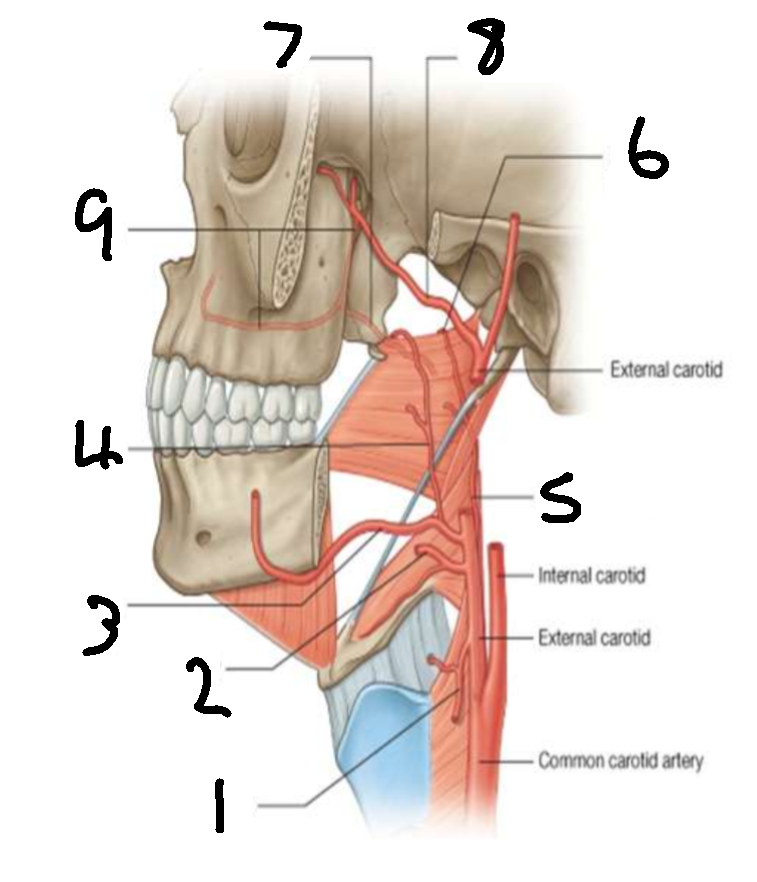

What is 1?

superior thyroid artery

What is 2?

lingual artery

What is 3?

facial artery

What is 4?

ascending palatine artery

What is 5?

ascending pharyngeal artery

What is 6?

palatine branch of pharyngeal artery

What is 7?

lesser palatine artery

What is 8?

maxillary artery

What is 9?

greater palatine artery